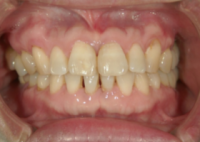

インプラントは、あごの骨に人工の歯の根(フィクスチャー・チタン製など)を埋め込み、その上に人工の歯を固定する、歯科の最先端医療技術です。当院では、最新のCT機械を導入し、以前にも増して、より精度の高い診断が可能となります。

青島歯科クリニックでは、歯が1本だけ無い場合から、全部無い場合まで、幅広く対応できます。

インプラント治療の最大のメリットは、今ある歯を守るということです。

噛み合わせなどで、お困りの方に是非、オススメいたします。